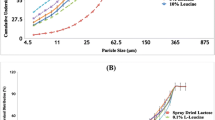

PCL microspheres were fabricated using the oil-in-water emulsion technique. The PCL microspheres were prepared in four different sizes by varying the concentration of the polymer and the speed of the stirring (Table I). The PCL microspheres were coated with MgSt and leucine. The particle size distribution of the PCL microspheres is shown in Fig. 3. The average VMD of the PCL microspheres were found to 25.5 ± 0.2 μm, 48.2 ± 0.1 μm, 104.4 ± 0.4 μm and 150.3 ± 0.4 μm (We will refer to these samples as 26 μm, 48 μm, 100 μm and 150 μm for brevity). The surface morphology of the PCL microspheres coated with MgSt and leucine was studied using SEM which showed that the PCL microspheres were spherical in shape and had irregular surface morphology (Figs. 4 and 5). Some crystals of MgSt appeared on the microparticles (Fig. 4) are from the solution of 1 % MgSt coating. The concentration of MgSt and Leucine in the particles shown in Figs. 4 and 5, respectively is 1 %. It was expected that MgSt would form a continuous thin layer on the surface of the microspheres; however, MgSt deposited in the form of crystals on the carrier surface (Fig. 4) due to the evaporation of the ethanol solvent which was used to dissolve MgSt. However, with 1.0 % leucine solution, the coatings were found to be uniform as opposed to the MgSt coatings (Fig. 5). It is important to note that the crystallization of MgSt occurred more from 2 % MgSt solution coating compared to that of 1 % MgSt solution (SEM data not shown in this paper).

The relationship between the FPF of SS from 1 % and 2 % MgSt coated PCL microspheres and the size of the microspheres is depicted in Fig. 8. It can be seen very clearly that as the size of the carrier increased there is an increase in the FPF of the drug from both 1 % and 2 % MgSt coated PCL microspheres. The reason behind this has been explained extensively above. There is also significant difference in the FPF of SS amongst the two concentrations of MgSt coatings (p < 0.05, n = 5). Similarly, the FPF of the drug from both 1 % and 2 % leucine coated PCL microspheres increased with the increase in the carrier size (Fig. 9); however there was no significant difference in the FPF of SS amongst the two concentrations of leucine coatings suggesting that the FPF of SS is independent of the concentration of the leucine coatings (over the values studied of 1 % and 2 %, p > 0.05, n = 5).

From Figs. 8 and 9 it is seen that the FPF increases linearly with the particle size, d. A parameter that also increases linearly with d is the mass per unit area of the particles, given by ρd/6. A commonly measure parameter for particles is the specific surface area which is 6/ρd so the FPF scales inversely with specific surface area.

where, k has units of cm2/g and is the slope of the plots in Figs. 8 and 9.

This gives a simple way of tailoring the performance of the dispersion system, by working with the particles having the lowest possible specific surface area.